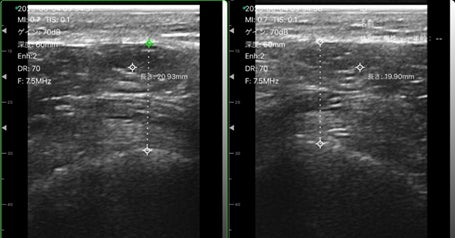

本製品は医療機器ではなく、スポーツ科学やフィットネス、ヘルスケア分野において効果的に筋肉の状態を評価できるツールです。中高年の足腰の状態を筋肉レベルで評価したり、左右の筋肉バランスの崩れや歩行に関わる筋肉の評価にご活用いただけます。

エコー画像をデータとして保存できるため、タブレットやスマートフォンの画像解析アプリを使って過去画像との比較や重畳表示などが可能です。長さ、面積、角度などの基本的な計測機能を搭載しており、筋肉の変化を視覚的に把握し、関係者と結果を共有できます。リハビリやトレーニング効果の評価、コンディション管理などに最適です。